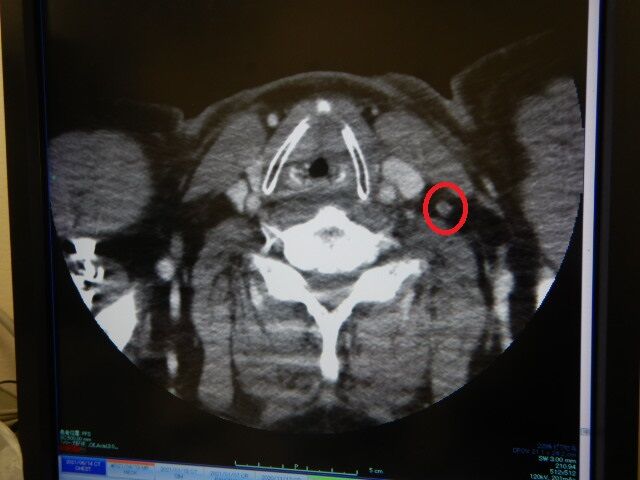

¿©»ö¤ò¤·¤Ê¤¬¤éÀèÆü¤ÎCT¸¡ºº¤Î·ë²Ì¤Ç

¤Á¤ç¤Ã¤Èµ¤¤Ë¤Ê¤ë¥ê¥ó¥ÑÀ᤬¼Ì¤Ã¤Æ¤¤¤¿»ö¤òÊó¹ð¡£

ÂèÆó²ó´â¥µ¥Ð¥¤¥Ð¡¼Äê´ü·ò¿ÇCT»£±Æ

Á°²ó¤ÏMRI»£±Æ¤Ç¡¢ÆÃ¤Ëµ¤¤Ë¤Ê¤ëʪ¤Ï̵¤«¤Ã¤¿¤Î¤Ç¤¹¤¬

º£²ó¤±ÆºÞ¤òÃí¼Í¤·¤Æ¤ÎCT»£±Æ¤Ç

¾¯¤·µ¤¤Ë¤Ê¤ë¥ê¥ó¥ÑÀ᤬½Ð¸½¡Ä¡£

Í׷вá´Ñ»¡¤È¤Ê¤Ã¤¿¡£

¤³¤Î¤Þ¤ÞÂ礤µ¤¬ÊѤï¤é¤Ê¤±¤ì¤ÐÎɤ¤¤Î¤Ç¤¹¤¬¡Ä¡£